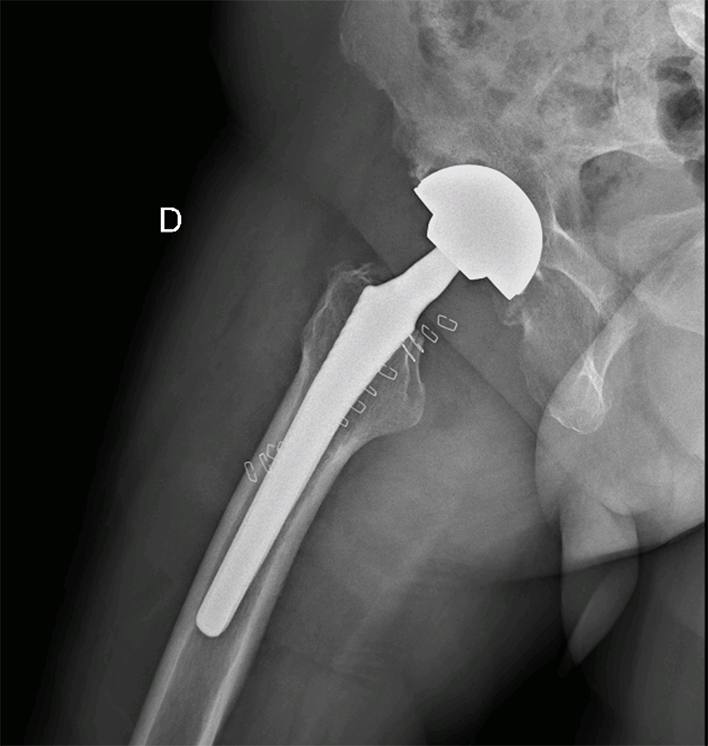

Radiographie bassin de face , Post opératoire après PTH droite

- Dr Dumoulin

Radiographie de hanche de profil après PTH droite